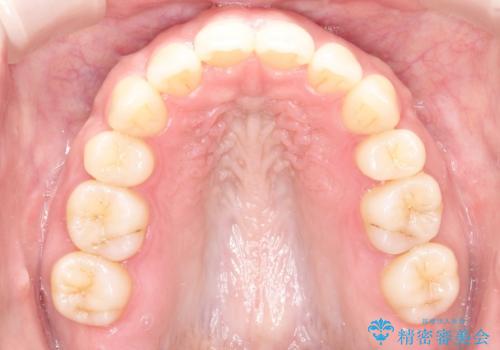

- 前歯の前突を主訴に来院されました。

下の前歯は癒合歯がある珍しいケースです。

治療に関しては小臼歯を4本抜歯して前歯を下げるような計画を立てて治療しました。

抜歯スペースの移動量を調整するために、矯正用アンカースクリューや親知らずを活用して治療を行いました。